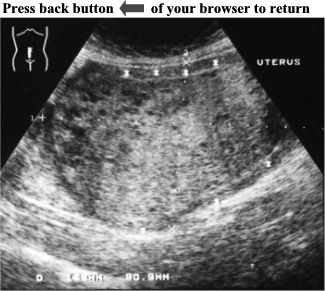

CASE

2:

Pelvic

ultrasound

of

this

female

patient

revealed

an

enlarged

uterus

(15.8cm

X

9.1cm).

There

was

a

large,

non-homogeneous,

solid

mass

filling

whole

uterus.

Several,

small

anechoic

structures

were

scattered

all

over

the

where

it

surrounded

by

normal

myometrium

(see

asterisks).